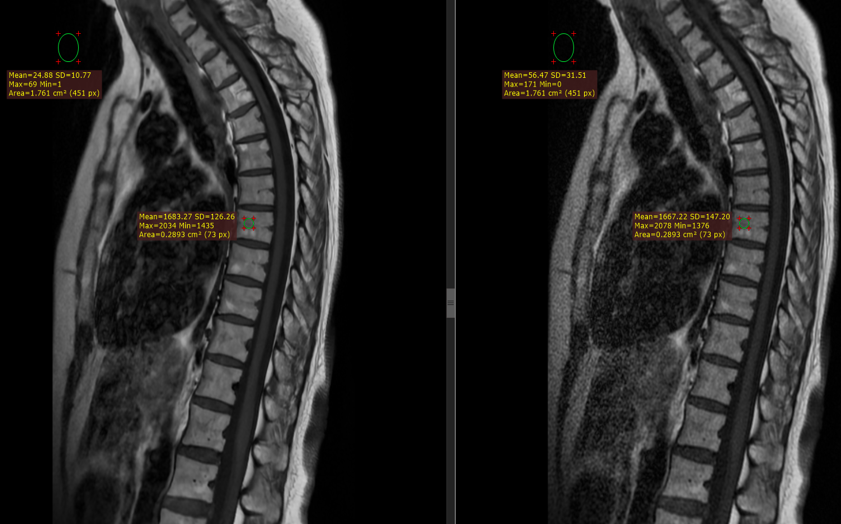

Figure 3 depicts a T2 weighted STIR image acquired with a matrix of 320 224 (top left) reconstructed with AirReconDL™ and the same image reconstructed conventionally (top right). The strength of the algorithm was set to “medium”. Upon acquiring and inspecting the image, we could not be sure if the line with the brighter signal was an artifact that resembles syringomyelia, or whether it was a finding. Therefore, we increased the resolution to 384x288, and set the strength of the algorithm to “high”, and increased the echo train length by 2, leading to a slight increase in acquisition time of 14 seconds, but with a final image of far superior image quality (bot left). This way, we were able to conclude that it was a normal finding, and neither an artifact nor a pathology. Same image reconstructed conventionally can be seen on the bot right.

Figure 3. Sagittal fast spin echo STIR images. Top row has AirReconDL™ strength set to medium with an acquisition matrix of 320x224. Bottom row has AirReconDL™ strength set to high, and acquisition matrix of 364x288, increased echo-train length by 2. Images on the left are reconstructed through the DL-based pipeline, and images on the right are reconstructed conventionally. SNR gains were 192% (top row), and 256% (bot row).